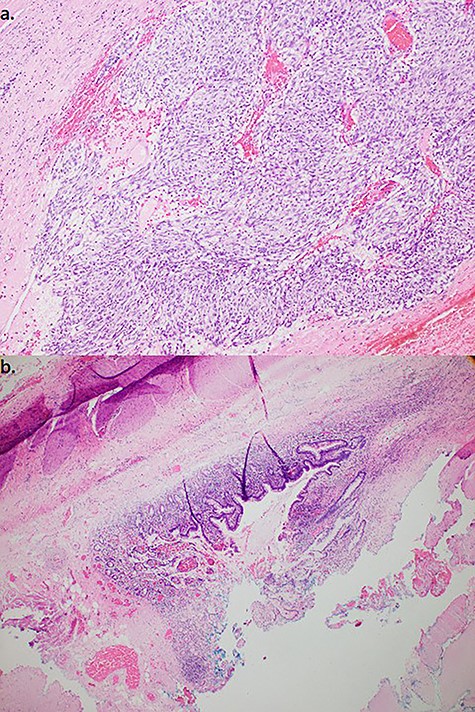

The following morning laparoscopy was performed with peritoneal washings taken for cytology. Present was a large round mass encased in adhesions to the right ovary and fallopian tube, small bowel, anterior rectum and sigmoid colon. A laparotomy was performed and the mass carefully dissected free. It appeared to arise on a pedicle from the small bowel, ~90 cm from the ileo-caecal junction. Histopathology revealed a largely infarcted solid lesion with areas characteristic for a GIST of the epithelioid type (positive for dog 1/CD 117 (KIT protein), negative for Sox 10/cytokeratin). (Fig. 3) The appearances were of a high-grade tumour with clear margins at stage pT3. The adjacent small bowel was normal with no evidence of invasion. The patient had an uncomplicated post-operative recovery.

(a). Resected specimen (100×) stained with Haematoxylin and Eosin demonstrated epitheloid type cells composed in nests and (b). adjacent small bowel mucosa/muscularis. Immunohistochemistry (not shown)—10% tumour cells positive for Ki67, positive staining for CD117, negative staining for CD68, SMA and desmin, consistent with GIST.